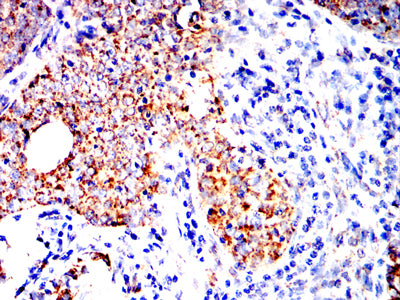

分类: 科研抗体货号: 32330别名: LCA; LY5; B220; CD45; L-CA; T200; GP180应用: IHC,FCM反应种属: Human